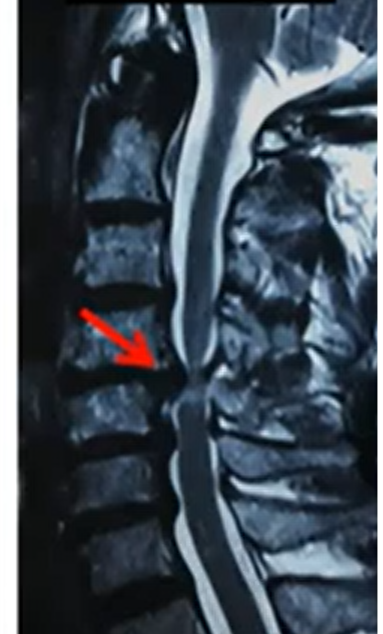

What is Cervical Spine Surgery?

Surgery on the neck part of the spine to relieve pressure on the spinal cord or nerves.

How is it Performed?

ACDF (Fusion)

Anterior Cervical Discectomy and Fusion to remove a damaged disc and fuse vertebrae.